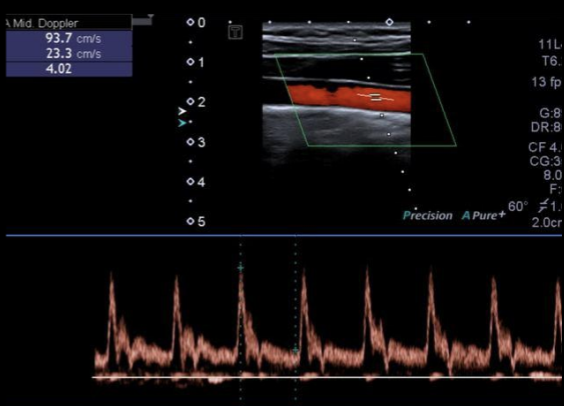

13

Q

A

Varice en Doppler